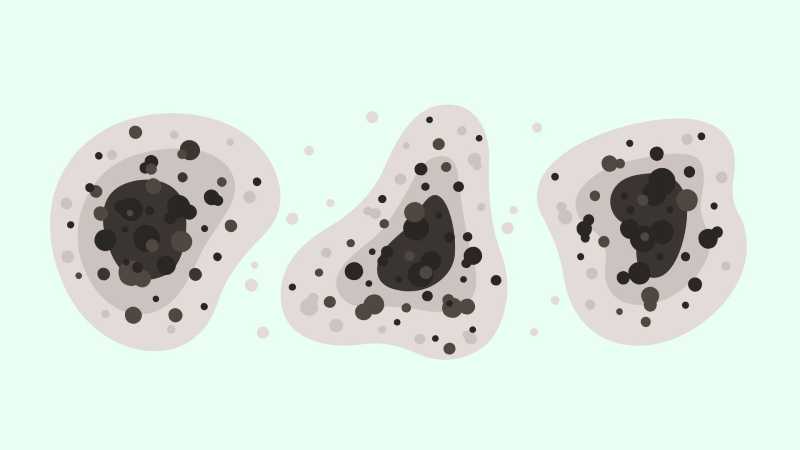

La mucormicosis es una infección rara, informada originalmente en la India, también conocida como “hongo negro”, y ahora se ha extendido por todo el mundo. Actualmente, múltiples autoridades de salud han reportado casos en Uruguay, Irak y México.

La mucormicosis es una infección oportunista causada por pequeños hongos. La Facultad de Medicina de la UNAM explica que se suele encontrar en suelos, plantas, pan, frutas y verduras en descomposición.

Los hongos pueden afectar a diferentes tejidos, principalmente: senos nasales, cerebro, pulmones y otras partes del cuerpo como el tracto gastrointestinal, la piel y los riñones.